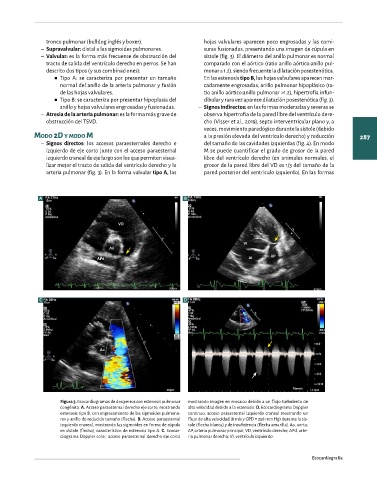

Figura 2. Ecocardiogramas 2D de un perro con estenosis valvular aórtica,

obtenidos mediante acceso paraesternal derecho de eje largo (A) y de eje Figura 3. Ecocardiogramas de dos perros con estenosis pulmonar mostrando imagen en mosaico debido a un flujo turbulento de

corto (B) mostrando engrosamiento de las sigmoides aórticas (flechas). congénita. A. Acceso paraesternal derecho eje corto, mostrando alta velocidad debido a la estenosis. D. Ecocardiograma Doppler

AI C. Ecocardiograma modo M al nivel aórtico, mostrando engrosamiento estenosis tipo B, con engrosamiento de las sigmoides pulmona- continuo, acceso paraesternal izquierdo craneal mostrando un

de las hojas valvulares y déficit de apertura durante la sístole (flecha). VI, res y anillo de reducido tamaño (flecha). B. Acceso paraesternal flujo de alta velocidad (8 m/s y GPD = 256 mm Hg) durante la sís-

ventrículo izquierdo; Ao, aorta ascendente; AI, atrio izquierdo; VD, ven- izquierdo craneal, mostrando las sigmoides en forma de cúpula tole (flecha blanca) y de insuficiencia (flecha amarilla). Ao, aorta;

trículo derecho. en sístole (flecha), característico de estenosis tipo A. C. Ecocar- AP, arteria pulmonar principal; VD, ventrículo derecho; APd, arte-

diograma Doppler color, acceso paraesternal derecho eje corto ria pulmonar derecha; VI, ventrículo izquierdo.